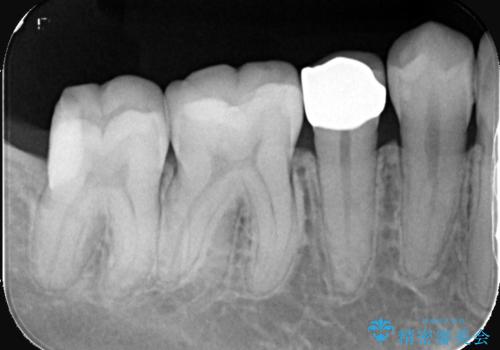

虫歯の部分のみを慎重に削除し、できる限り健康な歯質を残すように配慮しました。その後、強度があり適合性の高いセラミッククラウンを装着し、機能性と審美性の両方を確保。セラミックは変色しにくく、長期的な再発リスクも低減できるため、患者様にも安心していただけました。定期検診を継続することで、今後の虫歯リスクも管理していきます。